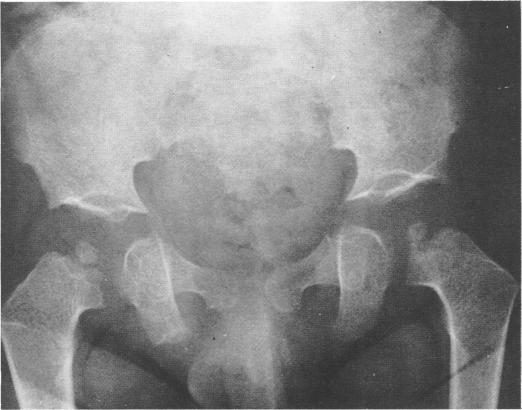

This survey reviews the diagnosis (predominantly radiological) of 32 cases of pseudoachondroplasia from 26 kindreds and illustrates the natural history and varying appearance of the disordered bone growth from infancy to adult life. In addition, an attempt has been made to detect phenotypic differences between autosomal dominant and recessive types (excluding isolated cases), analysing 10 kindreds of dominant inheritance (three in the current survey, seven from published reports) and six of recessive inheritance (three in the current survey, three from published reports). There appears to be no clinical or radiographical feature which clearly distinguishes them, but, using height as a criterion of severity, among those with autosomal recessive inheritance there was a disproportionate number of the most severely affected cases and there also appears to be very little intrafamilial variation. It is possible that pseudoachondroplasia can be subdivided into autosomal dominant mild and severe and autosomal recessive mild and severe, but full delineation must await elucidation of the basic defect at biochemical and molecular levels.

本调查回顾了来自26个家族的32例假软骨发育不全病例的诊断(主要是放射学诊断),并阐述了该疾病从婴儿期到成年期骨骼生长紊乱的自然病史及不同表现。此外,还尝试检测常染色体显性和隐性类型(不包括散发病例)之间的表型差异,分析了10个显性遗传家族(本次调查中有3个,已发表报告中有7个)和6个隐性遗传家族(本次调查中有3个,已发表报告中有3个)。似乎没有能明确区分它们的临床或影像学特征,但是,以身高作为严重程度的标准,在常染色体隐性遗传患者中,受影响最严重的病例比例过高,而且家族内差异似乎也很小。假软骨发育不全有可能可细分为常染色体显性轻度和重度以及常染色体隐性轻度和重度,但要进行全面分类,必须等待在生化和分子水平上阐明其基本缺陷。